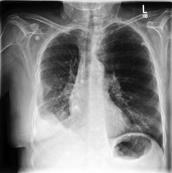

Large numbers of labeled medical images are essential for the accurate detection of anomalies, but manual annotation is labor-intensive and time-consuming. Self-supervised learning (SSL) is a training method to learn data-specific features without manual annotation. Several SSL-based models have been employed in medical image anomaly detection. These SSL methods effectively learn representations in several field-specific images, such as natural and industrial product images. However, owing to the requirement of medical expertise, typical SSL-based models are inefficient in medical image anomaly detection. We present an SSL-based model that enables anatomical structure-based unsupervised anomaly detection (UAD). The model employs the anatomy-aware pasting (AnatPaste) augmentation tool. AnatPaste employs a threshold-based lung segmentation pretext task to create anomalies in normal chest radiographs, which are used for model pretraining. These anomalies are similar to real anomalies and help the model recognize them. We evaluate our model on three opensource chest radiograph datasets. Our model exhibit area under curves (AUC) of 92.1%, 78.7%, and 81.9%, which are the highest among existing UAD models. This is the first SSL model to employ anatomical information as a pretext task. AnatPaste can be applied in various deep learning models and downstream tasks. It can be employed for other modalities by fixing appropriate segmentation. Our code is publicly available at: https://github.com/jun-sato/AnatPaste.